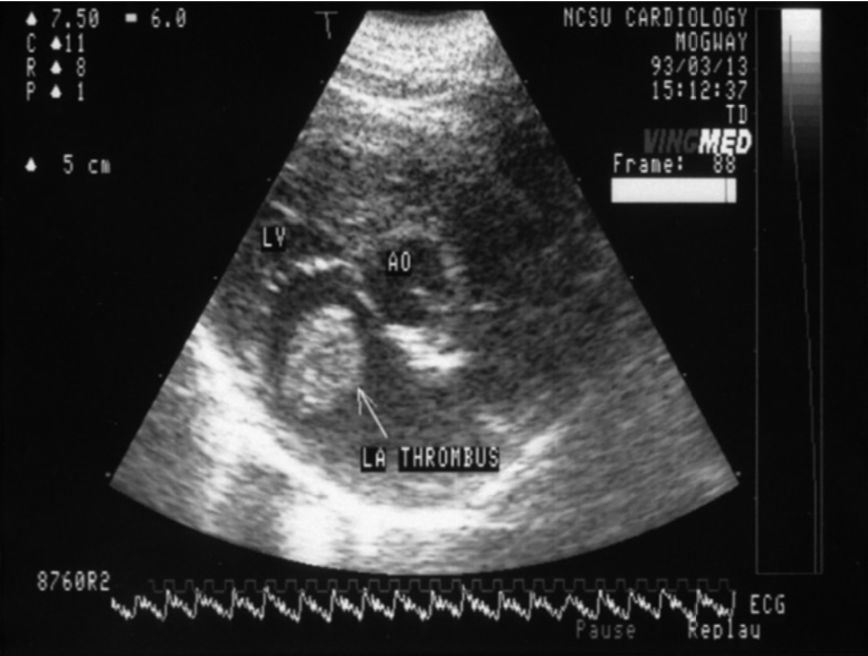

大多数患猫患有肥厚性心肌病,特征是左心室肥大、左心房增大,其他心脏病也有可能。

不论出现何种类型的心肌疾病,50%以上患有ATE的猫咪都有严重的左心房增大。

图示箭头处为左心房血栓

图片来自《Small Animal Emergency

and Critical Care》